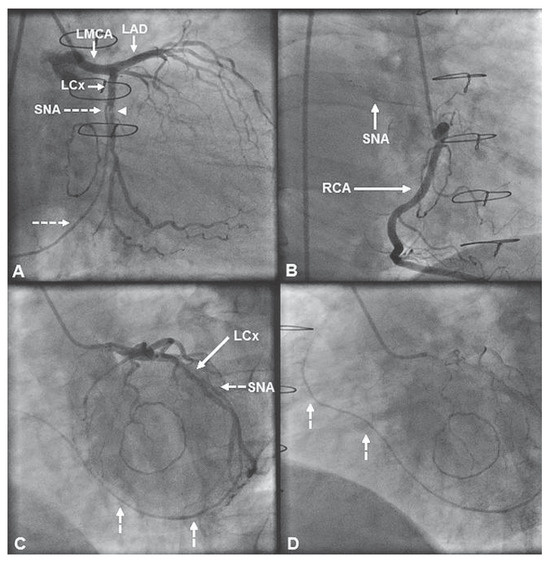

Retrocardiac Sinus Node Artery: A Previously Undescribed Anatomical Variation

Case report